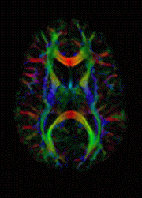

Diffusion MRI

Diffusion MRI measures the diffusion of water molecules in biological tissues.[161] Clinically, diffusion MRI is useful for the diagnoses of conditions (e.g., stroke) or neurological disorders (e.g., multiple sclerosis), and helps better understand the connectivity of white matter axons in the central nervous system.[162] In an isotropic medium (inside a glass of water for example), water molecules naturally move randomly according to turbulence and Brownian motion. In biological tissues however, where the Reynolds number is low enough for laminar flow, the diffusion may be anisotropic. For example, a molecule inside the axon of a neuron has a low probability of crossing the myelin membrane. Therefore, the molecule moves principally along the axis of the neural fiber. If it is known that molecules in a particular voxel diffuse principally in one direction, the assumption can be made that the majority of the fibers in this area are parallel to that direction.

The recent development of diffusion tensor imaging (DTI)[163] enables diffusion to be measured in multiple directions, and the fractional anisotropy in each direction to be calculated for each voxel. This enables researchers to make brain maps of fiber directions to examine the connectivity of different regions in the brain (using tractography) or to examine areas of neural degeneration and demyelination in diseases like multiple sclerosis.

Another application of diffusion MRI is diffusion-weighted imaging (DWI). Following an ischemic stroke, DWI is highly sensitive to the changes occurring in the lesion.[164] It is speculated that increases in restriction (barriers) to water diffusion, as a result of cytotoxic edema (cellular swelling), is responsible for the increase in signal on a DWI scan. The DWI enhancement appears within 5–10 minutes of the onset of stroke symptoms (as compared to computed tomography, which often does not detect changes of acute infarct for up to 4–6 hours) and remains for up to two weeks. Coupled with imaging of cerebral perfusion, researchers can highlight regions of "perfusion/diffusion mismatch" that may indicate regions capable of salvage by reperfusion therapy.